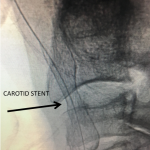

Figure 4.

Catheter angiography prior to angioplasty revealed critical stenosis (Figure 2). Angioplasty was therefore performed under local anesthesia with an embolic protection device deployed to catch any dislodged debris (Figure 3). After angioplasty, a stent was opened across the lesion to maintain long-term patency (Figure 4). Post-stent angiography showed smooth dilatation of the lesion. The patient’s aphasia continued to improve at his 6-week follow-up visit and duplex revealed no significant stenosis through the stent.